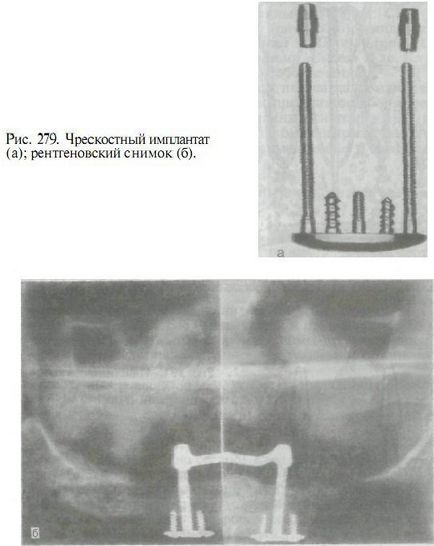

3. transosseous implantátum (transossalnye). A legtöbb e terjedési formájában Ilyen impiantátumok transmandibulyarnaya konzol tartalmaz egy lemez csatlakozik az alsó szélén a mandibula a frontális szakaszban, korlátozott mentális lyukak, és a csapokat kinyúló ezt a lemezt. Néhány a csapok (csavarok) viszünk be az állkapocs csont, intraossealis rögzítés végrehajtása szerkezete; Más, a rajta áthaladó, és a nyálkahártyán keresztül, található a szájüregben, és a hordozó, vagy további retenciós rögzítő elemeket protézisek. Vitalliya implantátumok titánból ötvözetek vagy arany (ábra. 279).